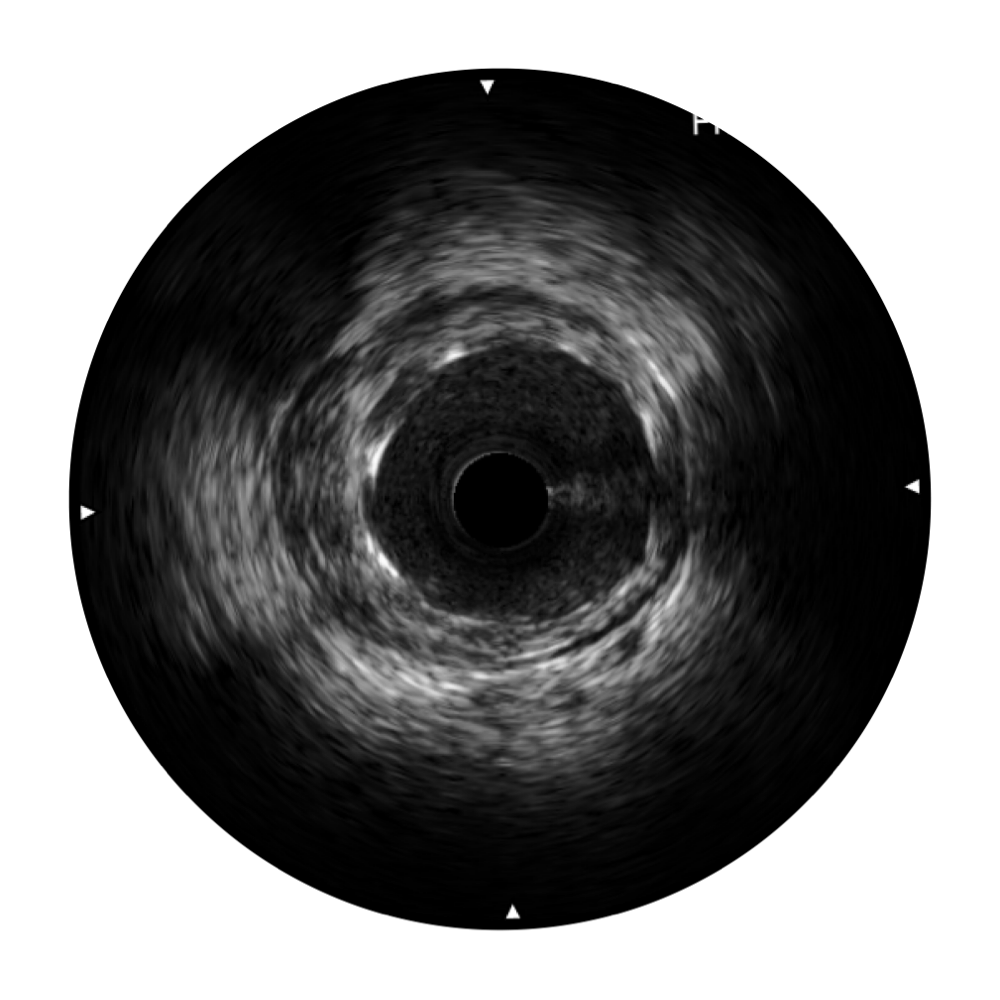

诸侯快讯官网宽频IVUS图像

传统IVUS图像

对比传统IVUS导管成像,诸侯快讯官网宽频IVUS图像的近场支架梁显影更细腻,远场中膜外血管仍清晰可辨,兼顾远中近,兼顾分辨力与穿透深度